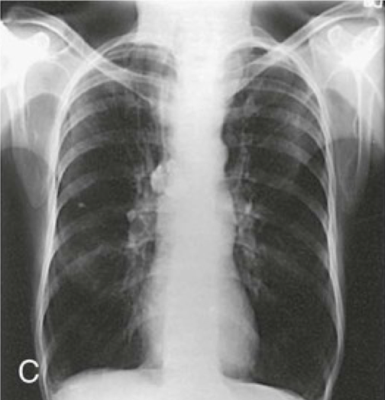

Identify the body habitus.

Answer

• Sthenic

• Asthenic

• Hyposthenic

• Hypersthenic